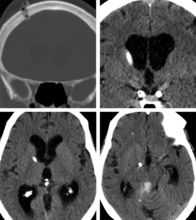

1.3 瞳孔的觀察人們常說眼睛是心靈之窗,其實不如說瞳孔是心靈之窗。瞳孔的變化常伴有意識狀況的改變。

瞳孔的觀察主要是觀察兩側(cè)瞳孔形狀、大小,對光反射是靈敏、遲鈍或消失。對觀察記錄應(yīng)進(jìn)行分析對比。

瞳孔的變化可反應(yīng)有無再出血和腦水腫。 1.4 顱內(nèi)壓的監(jiān)護(hù)顱內(nèi)壓監(jiān)護(hù)儀可連續(xù)觀察記錄病人的顱內(nèi)壓動態(tài)變化,是顱內(nèi)壓變化的可靠依據(jù)。